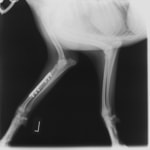

ペルシャ猫 11ヶ月齢 雄

他院にて左大腿骨遠位の成長板骨折(salter-harrisⅠ型)が認められており、治療相談を目的として来院。当院にて、キルシュナーワイヤーを用いたピンニングにより骨折部位の整復を行いました。術後の経過は良好で、現在も経過観察中です。

術前レントゲン